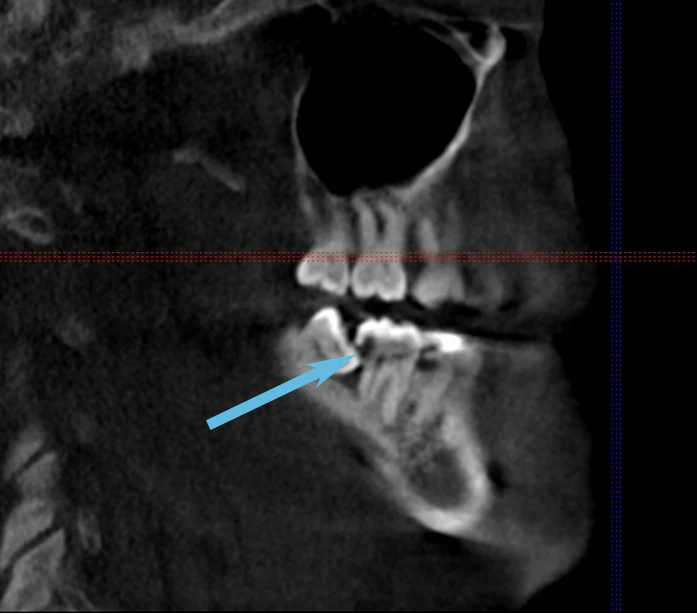

One lower wisdom tooth had tipped forward at nearly a 45-degree angle, wedging itself beneath the adjacent second molar. From another angle, the tooth appeared even more severely angled, closer to 60-80 degrees.

• A deep cavity on the back of the second molar

Eventually, the decay extended to the root surface of the second molar, as shown in the X-ray below.

Once decay reaches the root surface, the tooth often cannot be restored with a filling or crown. As a result, both the wisdom tooth and the otherwise healthy second molar had to be removed.